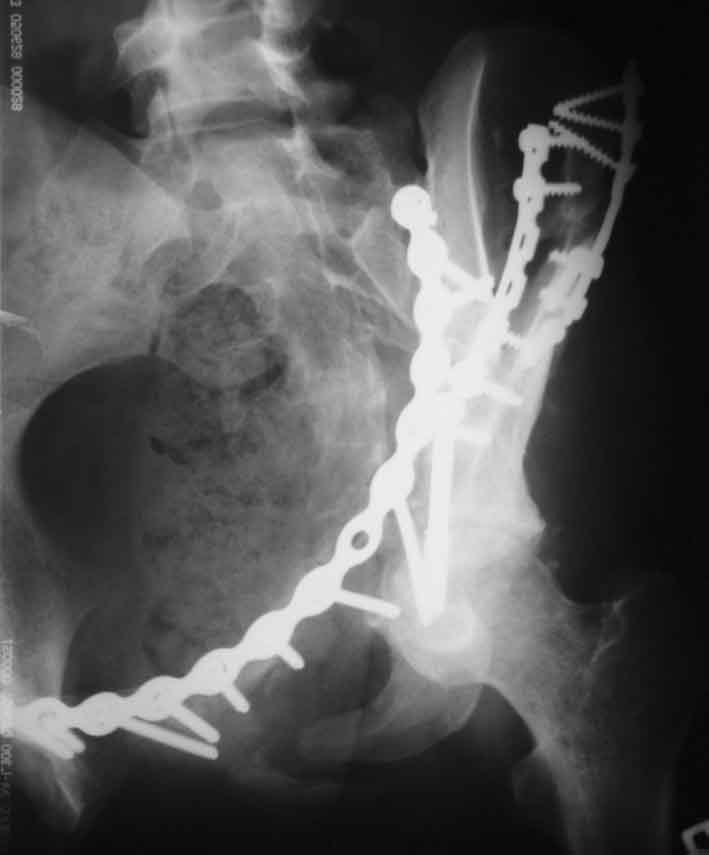

[Ortho] Рентгенограммы после операции

Запирательная